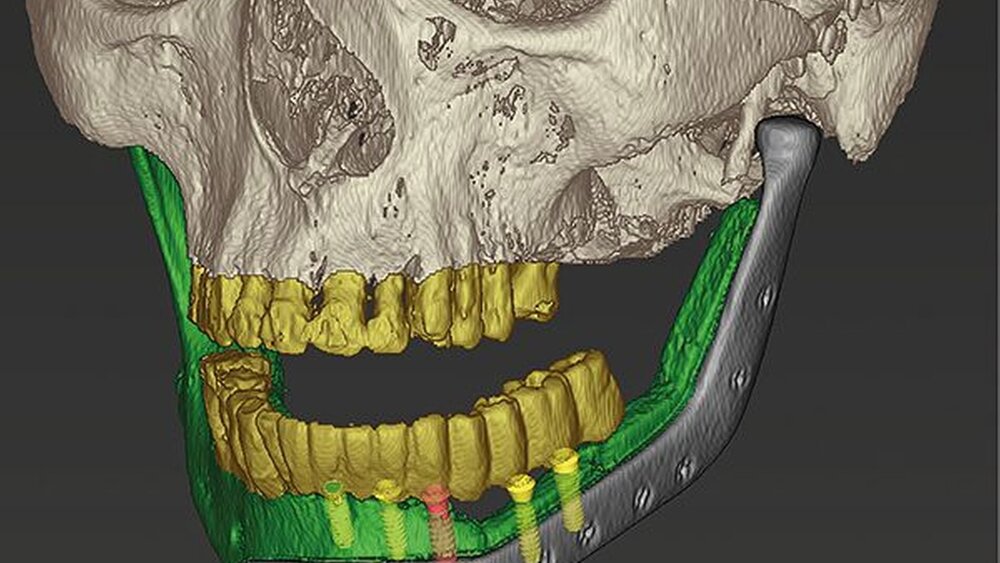

Die CT-Daten wurde in die Software der Firma 3D Systems (3D Systems, Littleton, USA) eingelesen und aufbereitet. Dadurch ist es möglich, relevante Areale zu segmentieren und bei der Planung virtuell frei zu positionieren. Dies kann in Abbildung 3 gut nachverfolgt werden. Die rotierte Mandibula wurde in ihre ursprüngliche Position und somit die Restbezahnung in Okklusion mit dem Oberkiefer gebracht.

Die neue Okklusion wird postoperativ mittels intermaxillärem Splint gesichert (Abbildung 4). In den Folgeschritten werden die Resektionsgrenzen festgelegt und die notwendigen Fibulasegmente angepasst (Abbildung 5).

Nachfolgend konnte im Backward-Planning mit der Planungssoftware coDiagnostiX (Dental Wings GmbH, Chemnitz) die möglichst optimale Position der Implantate in Bezug auf die transplantierte Fibula und Gegenkiefer festgelegt werden (Abbildung 12). Es erfolgte die Umwandlung in eine full guided-Bohrschablone für das Straumann Guided Surgery System.